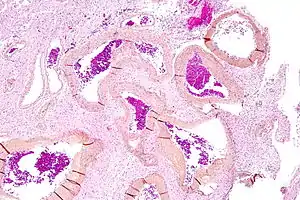

| Micrograph of an arteriovenous malformation in the brain. HPS stain. | |